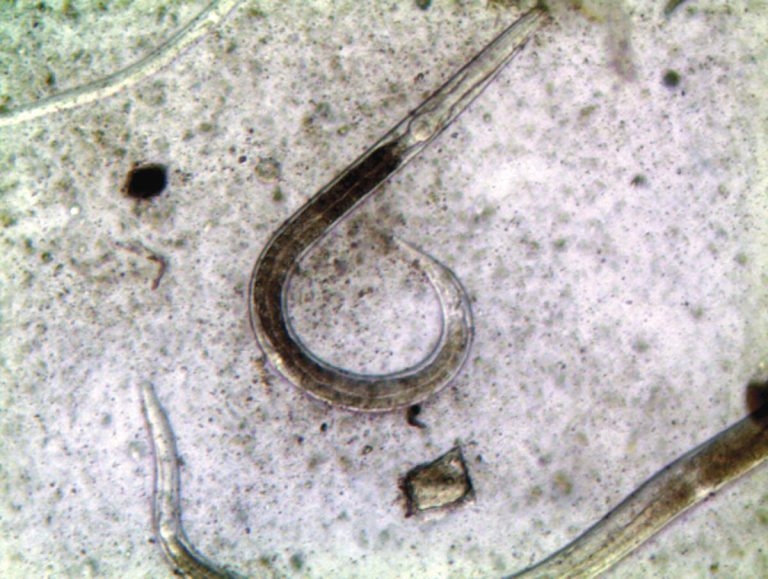

Figure 1. Photomicrograph of infective larvae of small redworms (cyathostomins).

These are the most common equine worms, with a prevalence rate that can reach 100% of horses. The larvae (Figure 1) burrow into the gut wall, where they lie dormant as encysted larvae. Subsequently, they mature and emerge from the gut wall in early spring, causing inflammation, diarrhoea, colic and death in up to 50% of affected horses. Since these encysted larvae are not mature and cannot produce eggs (Figure 2), they do not show up on a standard faecal egg count (FEC). A serological test based on IgG responses to cyathostomin larval antigens is available and can be used for the detection of these encysted larvae, complementing FECs.